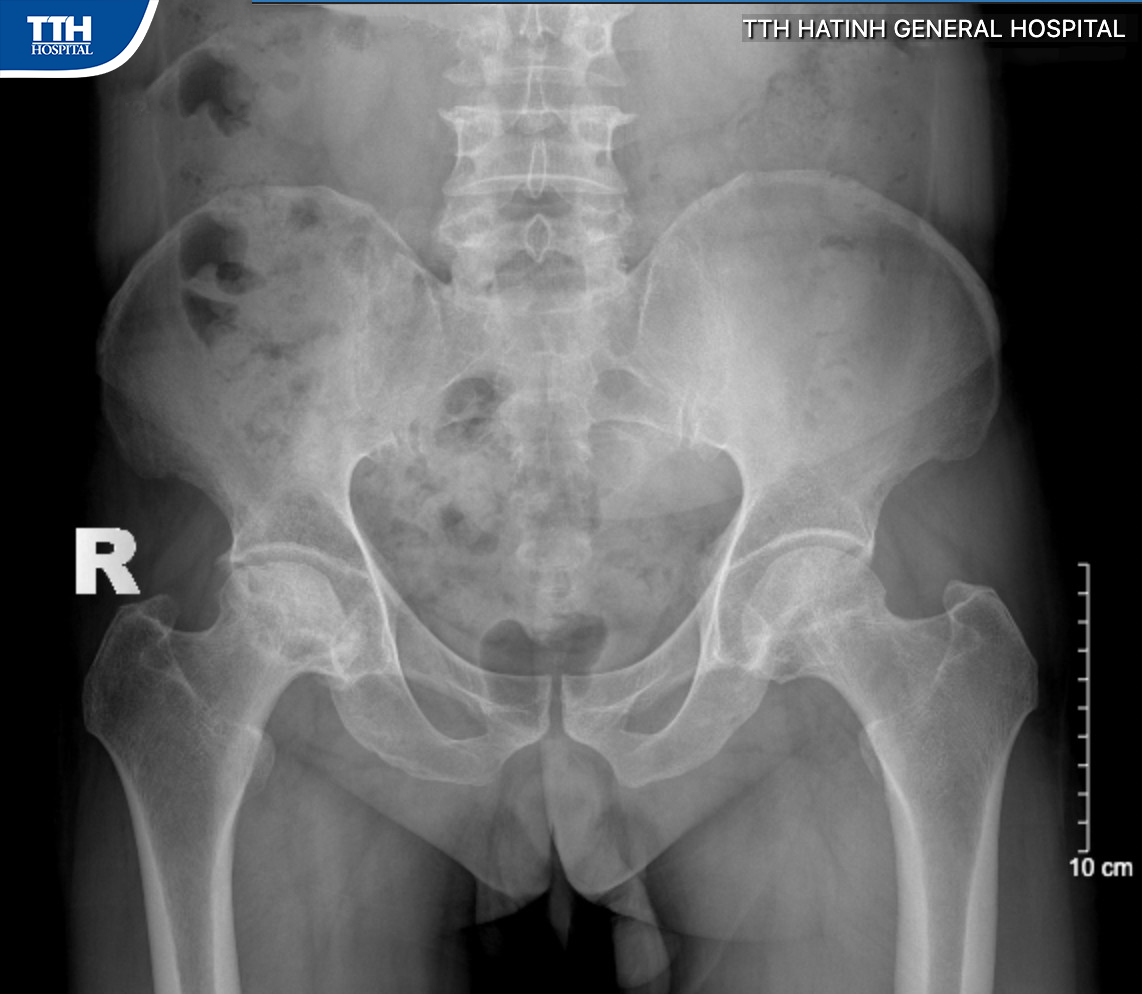

Sau khi thăm khám các chẩn đoán Cận lâm sàng được các Y Bác sĩ khoa CT– YHTT cho biết: ‘‘Bệnh nhân thoái hóa khớp háng bên phải và có chỉ định phẫu thuật thay khớp háng toàn phần. Ngay sau đó bệnh nhân được chỉ định phẫu thuật thay khớp háng bằng kỹ thuật SuperPath.